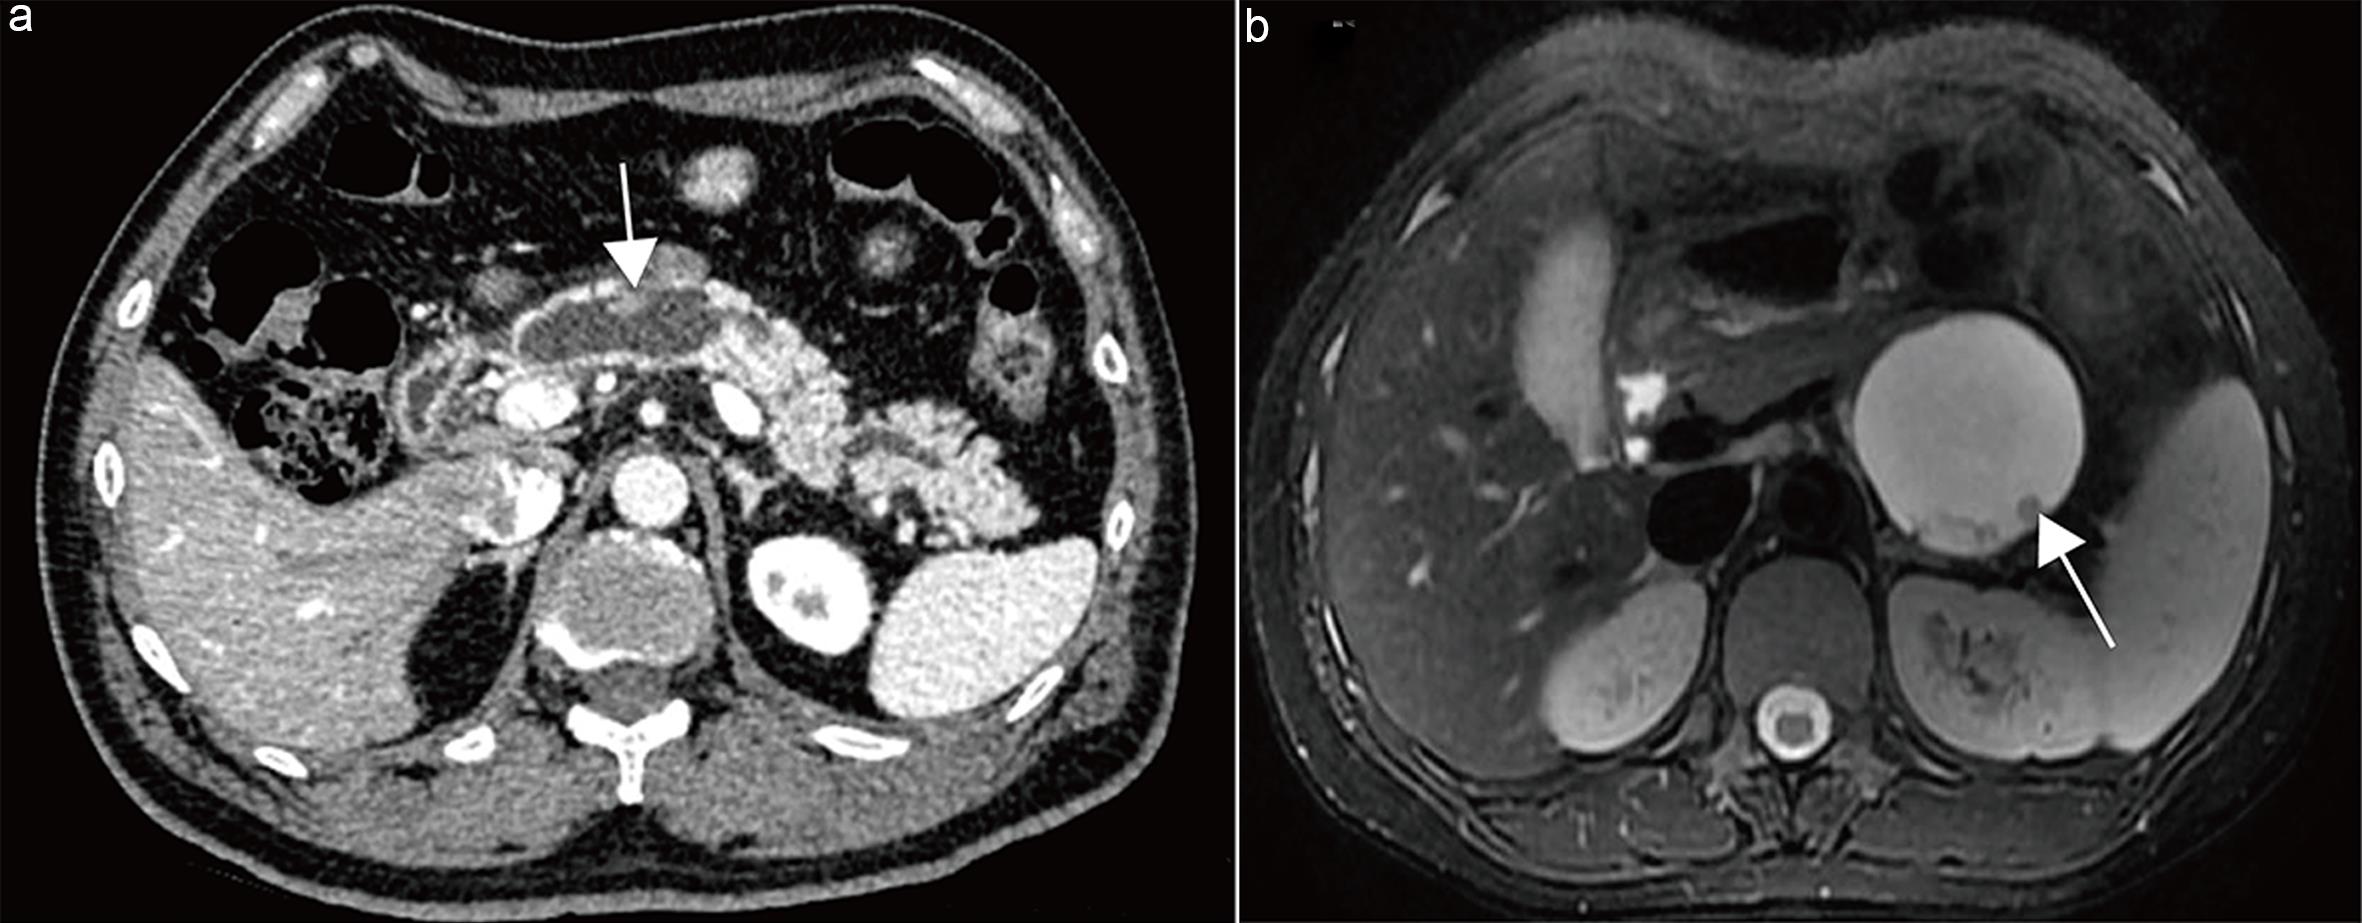

On CT, the pancreatic parenchymal phase demonstrates homogeneous enhancement of normal pancreatic tissue, while PCN cystic fluid remains unenhanced, providing optimal contrast to delineate tumor margins (Fig. 2a).15 On MRI, T2WI is highly sensitive to cystic components, with PCN cyst fluid exhibiting high signal intensity against the background of normal pancreatic parenchyma, allowing clear tumor boundary visualization (Fig. 2b). Furthermore, Dunn et al.16 demonstrated that measuring PCN size on coronal T2WI improves interobserver agreement.17

Measurement methods for pancreatic cystic neoplasms.

Fig. 2  Measurement methods for pancreatic cystic neoplasms.

(a) Mucinous cystic neoplasm in the pancreatic tail. Axial contrast-enhanced pancreatic parenchymal phase computed tomography (CT) image demonstrating the optimal plane for measurement. (b) Serous cystic neoplasm in the pancreatic tail. Axial T2-weighted image demonstrating the optimal plane for measurement. (c) Branch-duct intraductal papillary mucinous neoplasm (BD-IPMN) in the pancreatic head. Coronal T2-weighted image demonstrating the optimal plane for measurement.